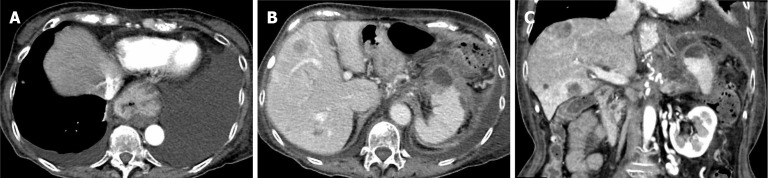

Case summary: A 74-year-old woman with pancreatic body and tail cancer developed fever and left-sided chest pain after multiple courses of chemotherapy. Computed tomography revealed fluid accumulation around the pancreatic tail and spleen along with a left pleural effusion. The effusion was diagnosed as reactive secondary to pancreatic fluid leakage. Endoscopic retrograde cholangiopancreatography identified irregular stenosis of the main pancreatic duct in the pancreatic body. Distal to the stenosis, the main ductal structure was nearly obliterated by the tumor. The contrast medium had leaked into the pancreatic fluid leakage area through several fine, disrupted ductal structures. The guidewire was successfully advanced through an extremely fine tract that was not the main contrast-filling route. Standard dilators failed to expand the rigid trans-tumoral tract. A second endoscopic retrograde cholangiopancreatography using a drill dilator successfully expanded the trans-tumoral tract, enabling endoscopic nasopancreatic drainage tube placement. Subsequently, the pancreatic fluid leakage and pleural effusion resolved.